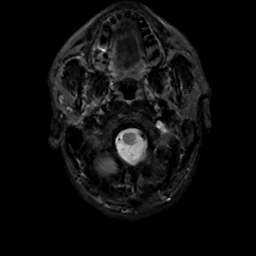

MR Study #12, May 12, 1991 -- Slice #2